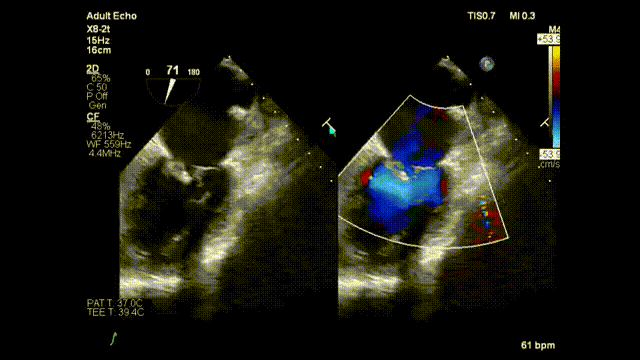

手术正式开始,魏来教授和杨晔医生在心超诊断科董丽莉教授、赵维鹏教授的协助下,仅一个多小时就顺利完成了E-Chord™的穿刺“发射任务”。4根人工腱索被送入朱女士的心脏,准确锚定在二尖瓣脱垂病变区域。然后在超声引导下精确调整人工腱索长度并固定在心尖,从而恢复了朱女士正常的二尖瓣关闭功能。手术完成后朱女士二尖瓣反流立即由重度减少为微量;同时左房平均压明显改善,由术前42mmHg下降到24mmHg。手术全程在超声引导下进行,操作便捷可控,无放射线,心脏不停跳,无需体外循环,创伤小,不出血,恢复快。患者术后2小时即拔除气管插管并返回病房,第二天即可下床活动。

术中器械顶住二尖瓣并击发,锚定人工腱索